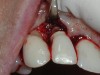

A guided bone regeneration (GBR) approach involving implant surface detoxification (Figure 2), placement of a bone graft combined with a barrier membrane (Figure 3 and Figure 4), and use of a systemic antibiotic has demonstrated the most predictable improvement in peri-implant parameters after destruction of supporting bone. GBR procedures demonstrated reductions in probing depth of 3.16 mm and 2.1 mm of radiographic bone fill in a recent systematic review and meta-analysis of 21 studies by Chan et al.21 Froum and Rosen22 defined a specific protocol based on reentry evaluation of previously treated peri-implantitis sites that included the use of rhPDGF-BB with freeze-dried mineralized bone and the addition of a resorbable membrane. Nonresorbable Gore-Tex® sutures were used to approximate the gingival tissue and were retained in place for 2 weeks. The patient was also kept on chlorhexidine for 2 weeks postoperatively. The reentry photographs from this report are quite impressive. However, the authors do caution the interpretation of re-osseointegration (Figure 5 and Figure 6).

Fig 2. Removal of cement and detoxification with tetracycline hydrochloride.

Figure 2

Fig 3. A freeze-dried bone allograft was placed.

Figure 3

Fig 4. A resorbable collagen barrier was placed.

Figure 4